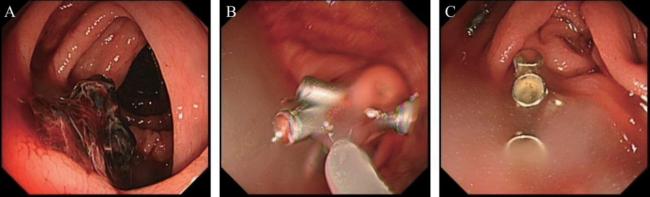

1.针对肠息肉摘除术后出血的应用

患者男,48岁,升结肠息肉EMR切除术后,术后反复出血,经2次内镜下钛夹夹闭止血后再次出血,第3次进行内镜下止血粉治疗后成功止血,见图1

图1 肠息肉摘除术后止血

A:升结肠处原氩离子凝固术处出血;B:创面予以钛夹缝合,予以复合微孔多聚糖止血粉喷洒;C:创面止血完成